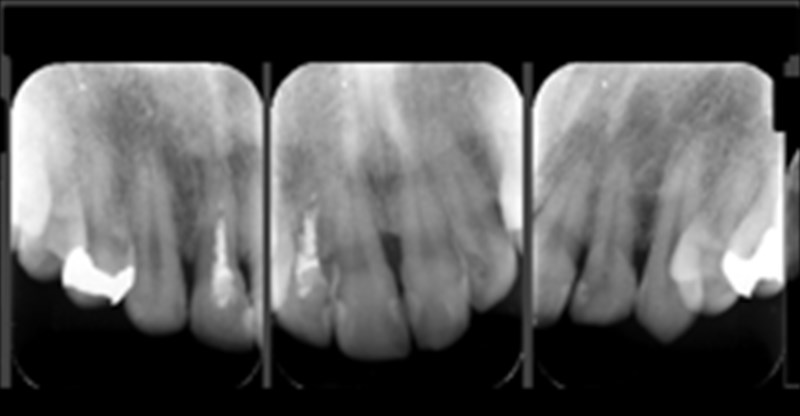

術後のレントゲン

術前にあった骨の炎症がレントゲンからも消えています。